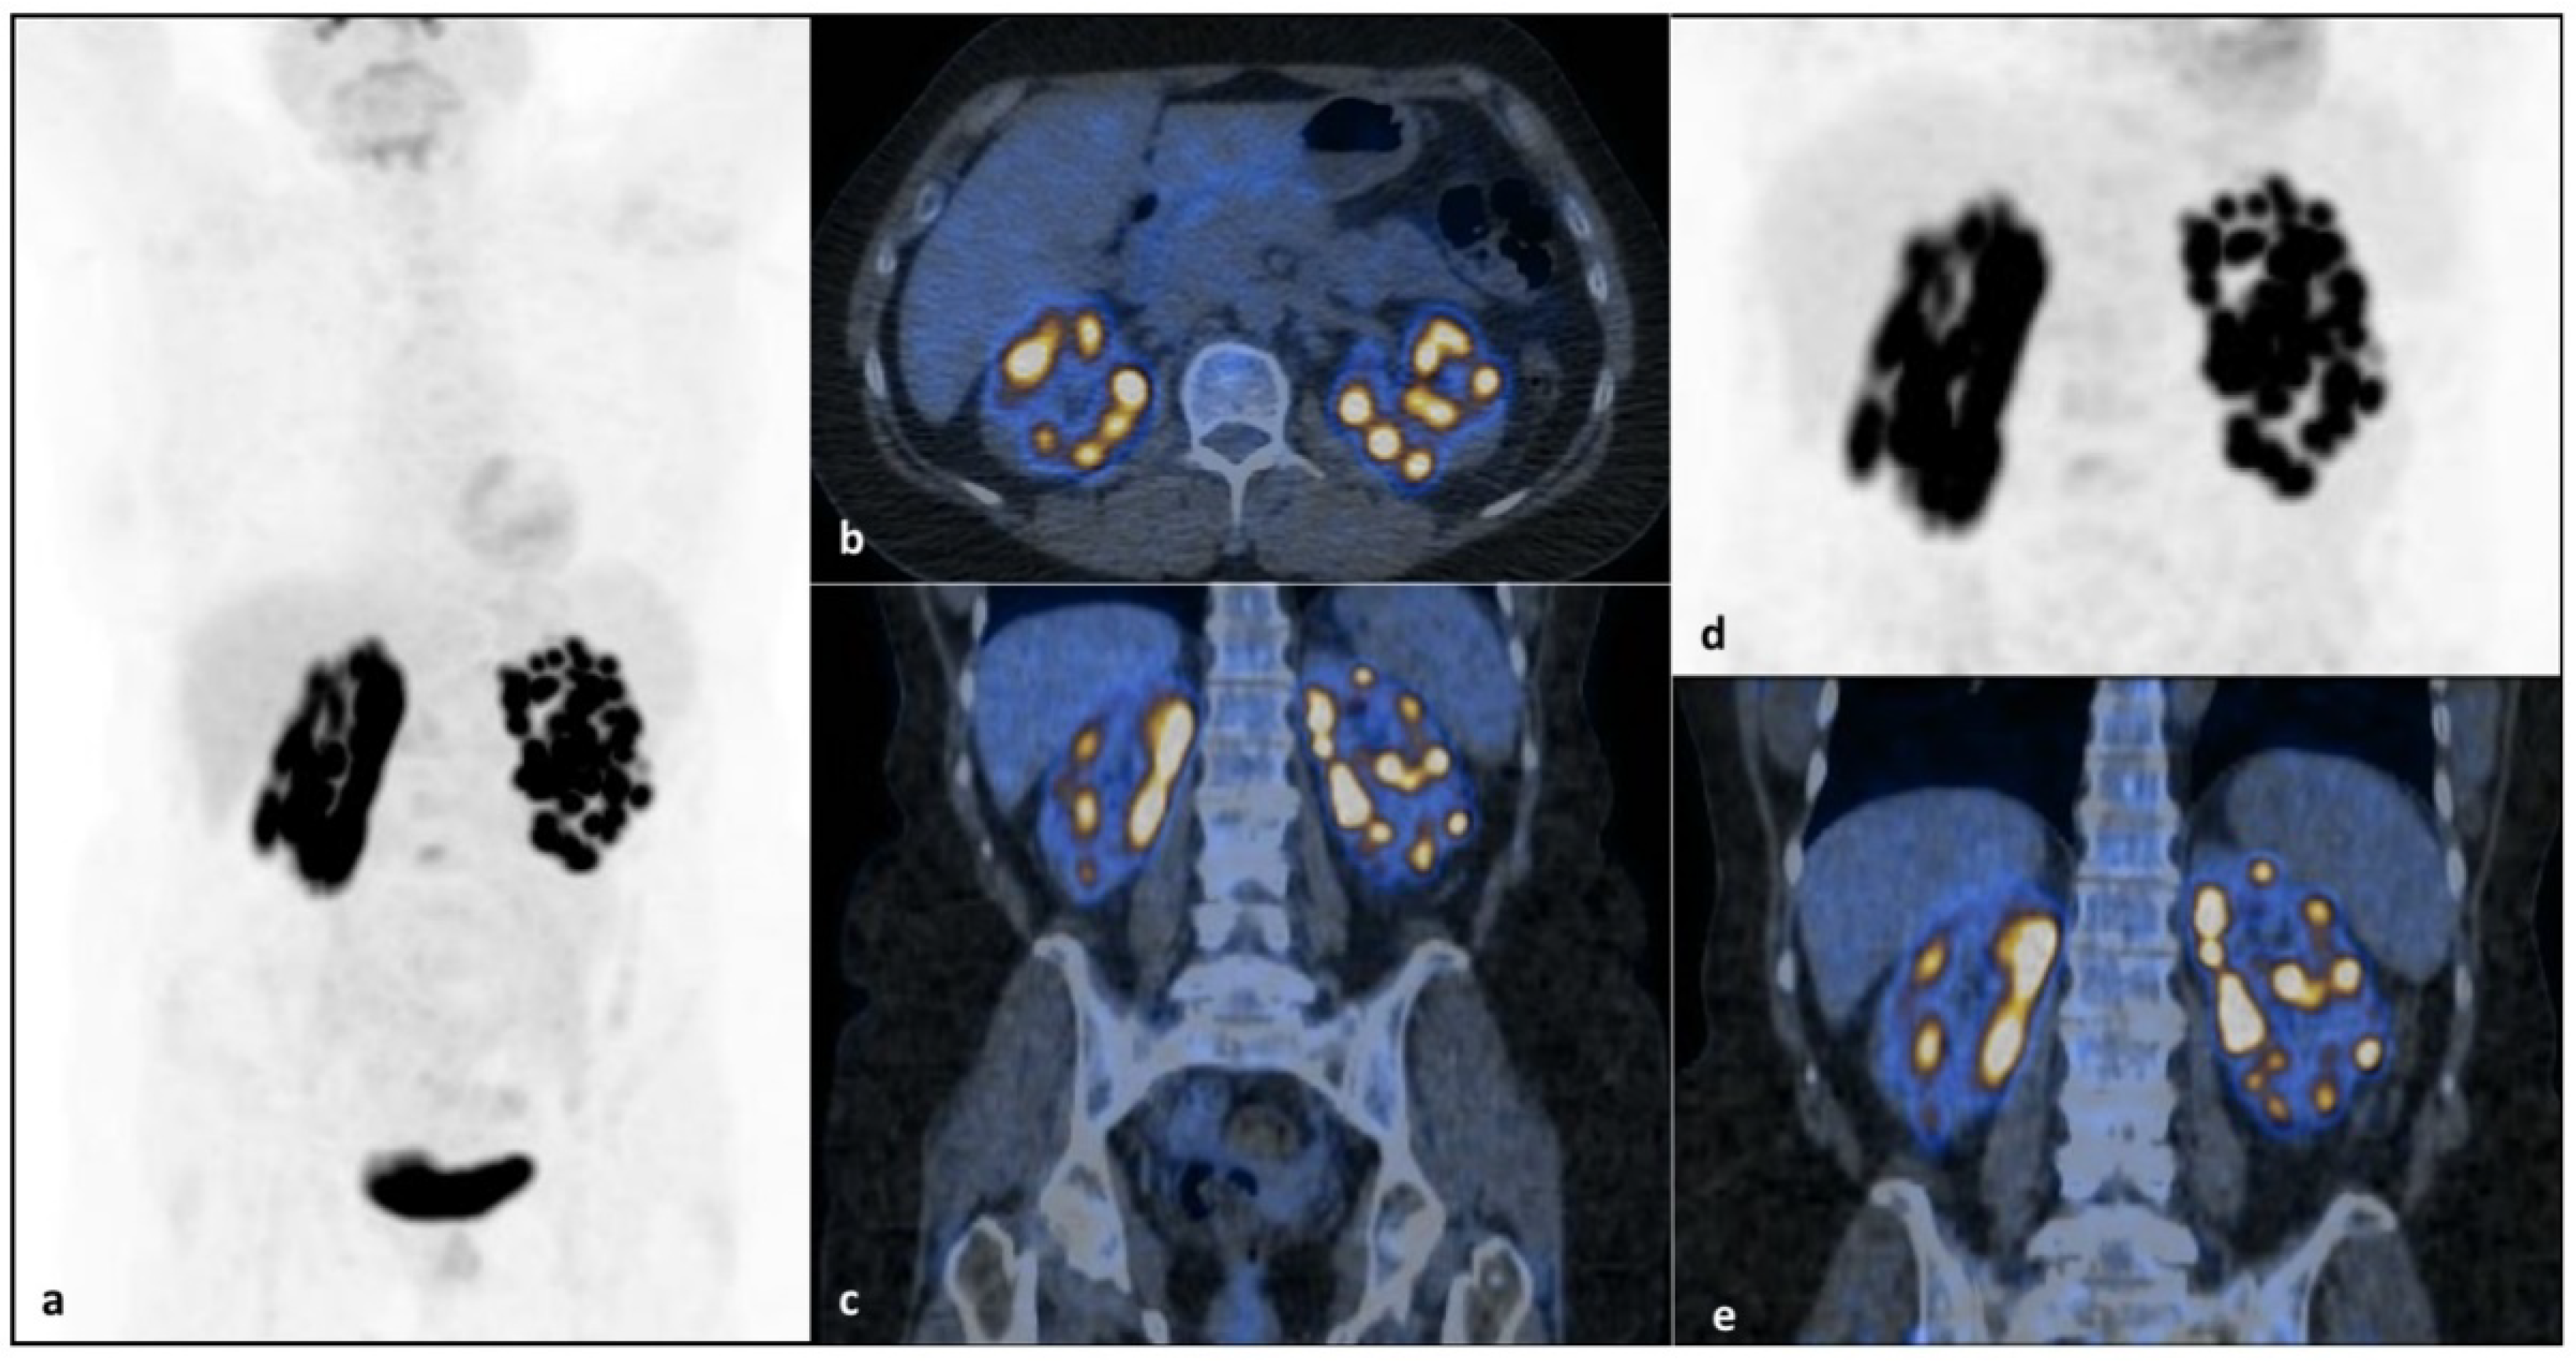

Primary, Bilateral and Diffuse Renal Non-Hodgkin’s Lymphoma in a Young Woman Suffering from Turner Syndrome

2. Case Report